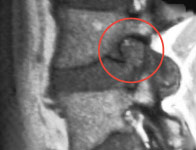

mri_bandscheibenvorfall

Abb. 2

Im MRI wird ein deutlicher, seitlicher Vorfall im Bereich des vierten und fünften Lendenwirbels sichtbar, der nach oben auf die Nervenwurzel drückt. Das seitliche Nervenfenster wird weitgehend vom Vorfall ausgefüllt.

Frau E., pensionierte Kindergärtnerin, fühlt sich mit 67 Jahren sehr rüstig, unternimmt gerne Wanderungen und besorgt ihren Zweipersonenhaushalt selbständig. Die Wirbelsäule machte bisher problemlos mit. Anlässlich des Einbettens einer neuen Matratze verspürt sie bei einer Ausdrehbewegung des Oberkörpers einen akut stechenden Schmerz über der Lendenwirbelsäule, der nicht ganz abklingen will. In der darauffolgenden Nacht plagt sie ein brennender, ins rechte Schienbein ausstrahlender Schmerz, der auf verfügbare lokal einsetzbare Medikamente kaum anspricht. Am Morgen hat sie Mühe, das rechte Bein zu belasten. Treppab sackt ihr gegen Mittag das rechte Knie durch. Sie sucht ihren Hausarzt auf, der ihr zunächst Cortison verschreibt. Da innerhalb von drei Tagen eine Besserung ausbleibt und die Knieschwäche weiter zunimmt, veranlasst der Hausarzt ein Kernspintomogramm (MRI). Dieses zeigt einen seitlichen Bandscheibenvorfall, rechts, zwischen dem vierten und fünften Lendenwirbel (Abb. 2). Der vierte Lendennerv, zuständig für Kraftsteuerung am Oberschenkel und am Knie sowie für die Gefühlszone ventral am Schienbein, wird – übereinstimmend mit den Symptomen – durch den Vorfall abgedrückt.